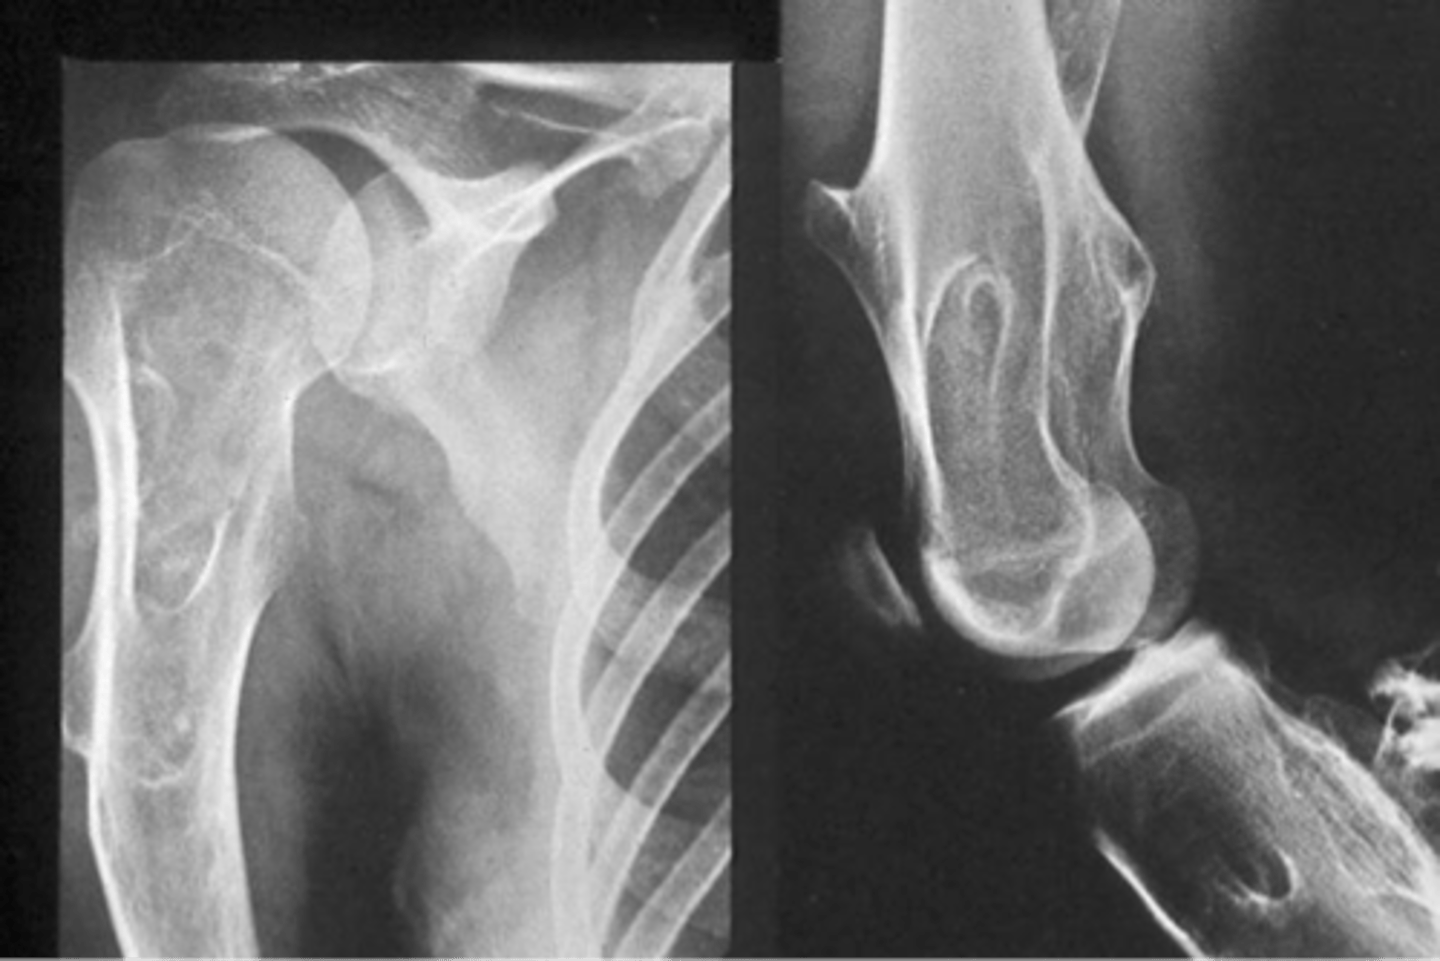

Solitary osteochondroma

- Most common benign skeletal growth or tumor

- 50% of all benign bone tumors

- 10-15% of all primary bone tumors

- 75% <20 y.o.

- M:F, 2:1

- Malignant transformation <1%

<p>- Most common benign skeletal growth or tumor</p><p>- 50% of all benign bone tumors</p><p>- 10-15% of all primary bone tumors</p><p>- 75% &lt;20 y.o.</p><p>- M:F, 2:1</p><p>- Malignant transformation &lt;1%</p>

7

New cards

- Mostly asymptomatic

- Painless, hard mass

- Stalk may fracture

- Pain and rapid growth = malignant transformation

State the clinical features of solitary osteochondroma

<p>State the clinical features of solitary osteochondroma</p>

8

Pedunculated

_____ solitary osteochondroma:

- Metaphyseal

- Thin, elongated stalk

- Cortex and medulla continuous

- Calcified cap

- Projects away from joint

- Lucent when en face (on end)

<p>_____ solitary osteochondroma:</p><p>- Metaphyseal</p><p>- Thin, elongated stalk</p><p>- Cortex and medulla continuous</p><p>- Calcified cap</p><p>- Projects away from joint</p><p>- Lucent when en face (on end)</p>

9

Sessile

- Broad-based

- Wide, broad metaphysis

- Cartilage cap uncommon

<p>_____ solitary osteochondroma:</p><p>- Broad-based</p><p>- Metaphyseal</p><p>- Wide, broad metaphysis</p><p>- Lucent when en face (on end)</p><p>- Cartilage cap uncommon</p>